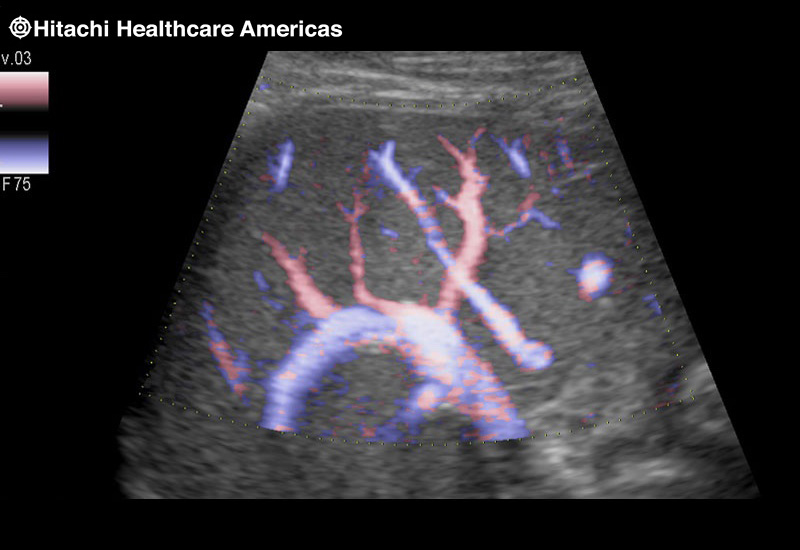

Giving the surgeon complete control

The Fujifilm Healthcare transducer utilizes the full benefits of the Wrist Articulation™ of the robotic instruments to capture real-time ultrasound imaging even at complex angles and difficult-to-reach areas.

The next level in Robotic Ultrasound

Full wrist articulation with optimized functional length.

A critical function of robotic ultrasound guidance is tumor margin identification. Fujifilm's family of robotic probes all have the optimum location of the attaching mechanism that allows for full wrist articulation of the probe. The result is an increased confidence that the tumor margins have been completely identified.